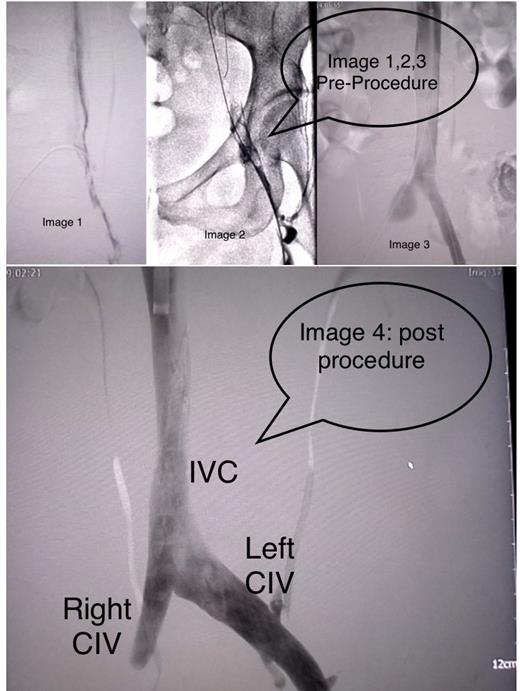

Invasive Radiology was consulted and she had a venogram and intravascular ultrasound (IVUS) which showed high-grade right common iliac vein and IVC stenosis (>90%) at L4 superior endplate. Iliac stenting and angioplasty improved iliac and inferior IVC diameters. Patient also underwent thrombectomy & IVC filter placement. The diagnostic venography revealed a popliteal-to-proximal femoral vein rethrombosis. This was treated with tissue plasminogen activator (TPA) by 8 French power pulse AngioJet and a mechanical thrombectomy. This resulted in partial clearing of the common femoral vein with persistent narrowing and thrombosis of the popliteal vein. TPA was infused at 1 mg/hour with a 5 French McNamara lysis catheter over the popliteal region.Patient transferred to ICU for overnight intravenous thrombolysis.